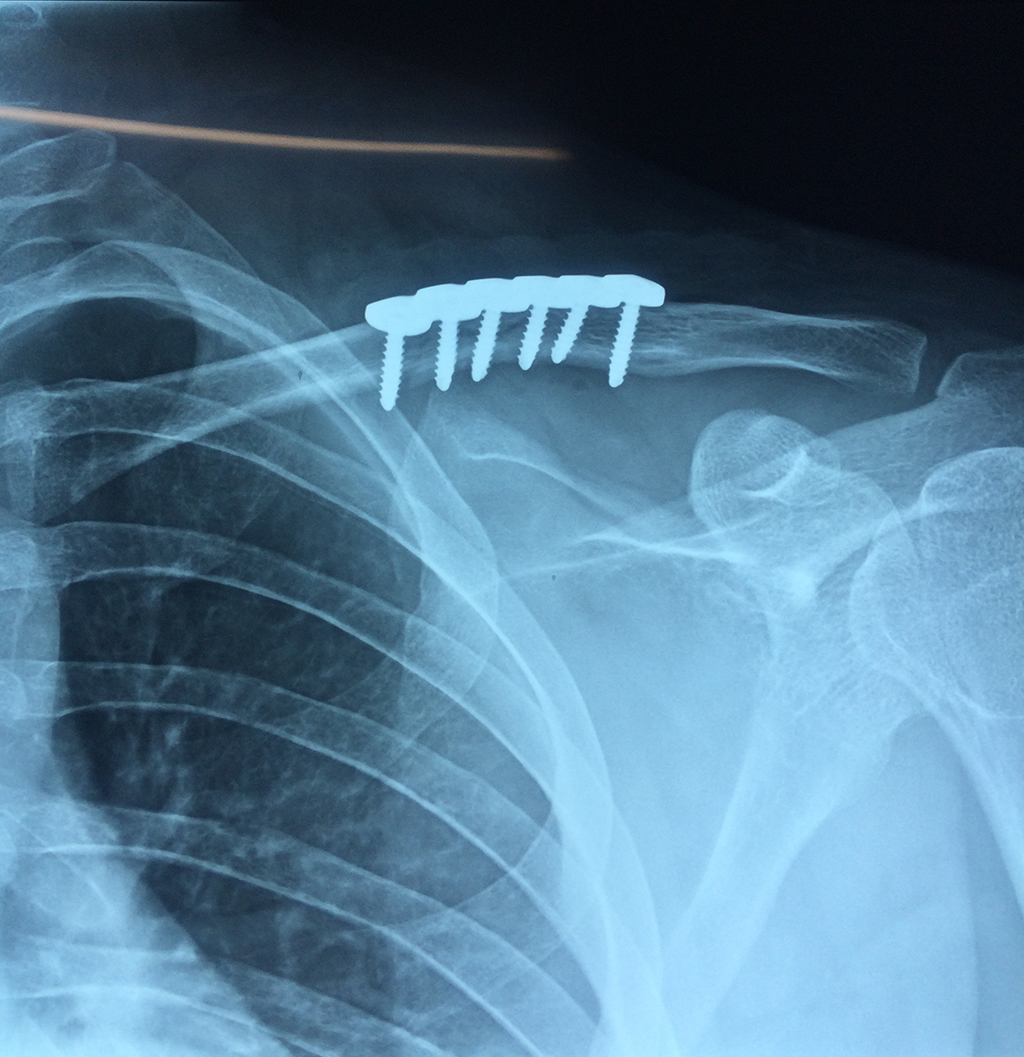

Cirugías de Calcaneo - Clavícula

La clavícula es un hueso largo, con forma de "S" itálica, situado en la parte anterosuperior del tórax. Junto con la escápula forman la cintura escapular. Se puede palpar por toda su longitud y se extiende del esternón al acromion de la escápula, siguiendo una dirección oblicua lateral y posterior.

Se considera el único medio de unión entre el miembro superior y el tórax. A pesar de su aspecto, similar al de un hueso largo, posee una estructura semejante a la de un hueso plano, ya que carece de epífisis y de diáfisis, lo que la harían entrar dentro de la clasificación de hueso largo. Carece de un canal medular propiamente dicho.